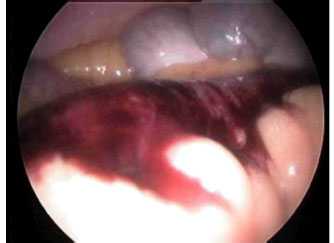

Помимо этого, для предварительной оценки зоны несостоятельности анастомоза, ее размеров и расположения всем пациентам выполнена ЭГДС (рис. 3). Рис. 3. Эндоскопическая картина у пациента после трансхиатальной эзофагэктомии с пластикой пищевода изоперистальтической желудочной трубкой. Желтыми стрелками указан просвет желудочной трубки, черными — зона несостоятельности анастомоза.

На 3—5-е сутки удаляли аспирационную систему и эндоскопически контролировали динамику размеров дефекта. При визуальном отсутствии несостоятельности (рис. 9) Рис. 9. Эндоскопическая картина у пациента после резекции желудка, нижней трети пищевода, интерпозиции сегмента тощей кишки по типу еюногастропластики, несостоятельности эзофагоеюноанастомоза и 3 сеансов лечения с помощью вакуумно-аспирационной системы. Полное закрытие дефекта в зоне пищеводного соустья. ВАС удаляли и выполняли контрольное рентгенологическое исследование с водорастворимым контрастом. При сохранении дефекта ВАС устанавливали повторно.